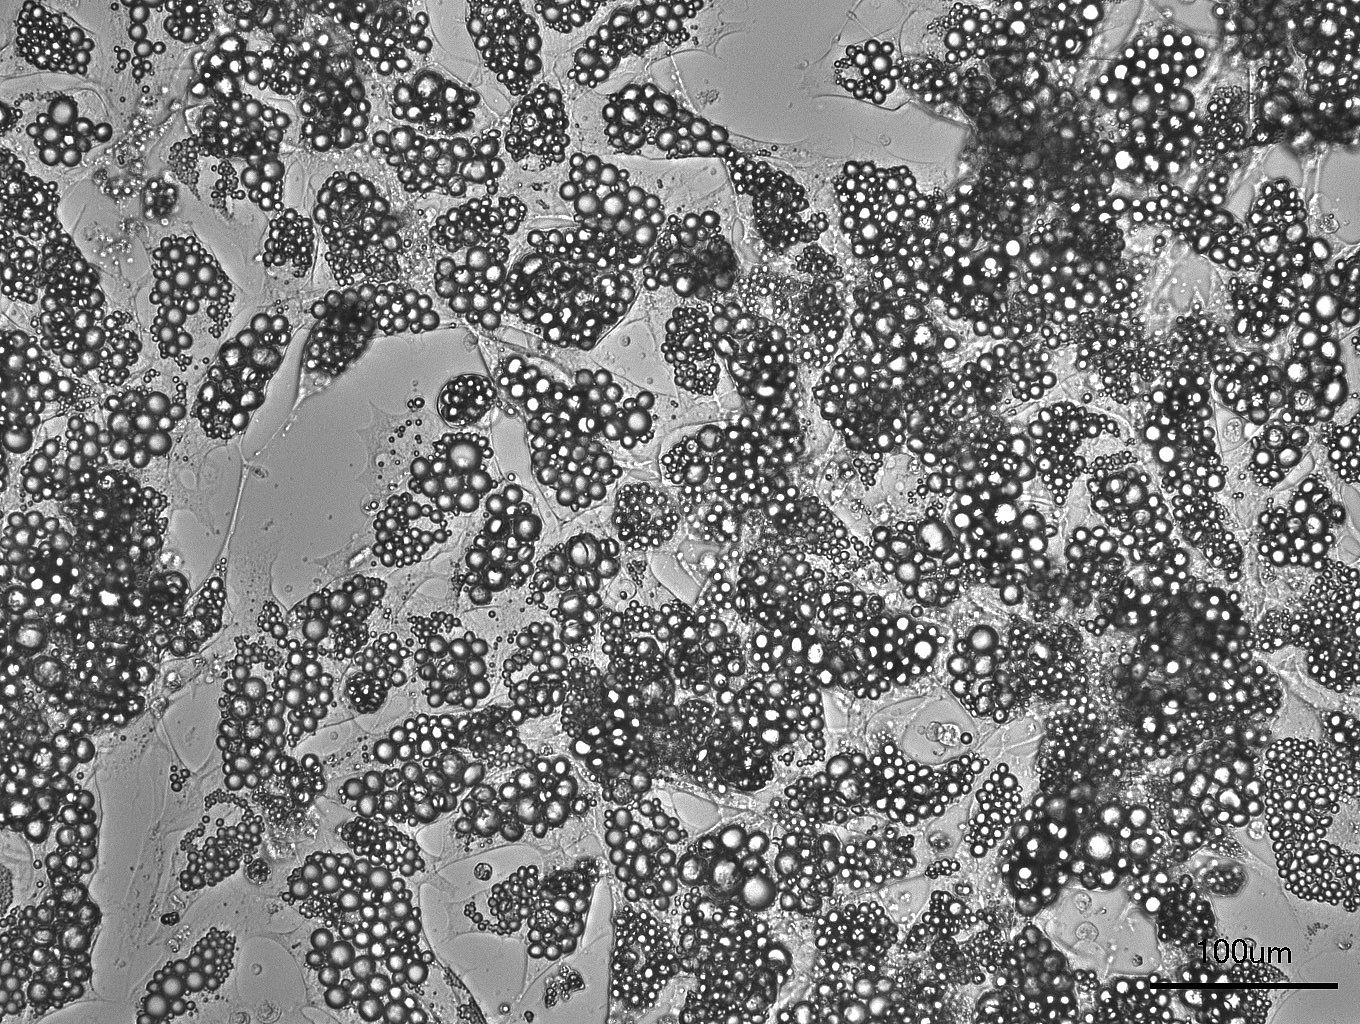

Die Forschenden analysierten genetische Sequenzen von 7719 Menschen mit extremer frühkindlicher Adipositas. Bei 316 Personen und 461 ihrer Familienmitglieder wiesen sie Veränderungen in MC4R nach. Der Vergleich mit Daten von mehr als 330 000 Kontrollpersonen ohne solche Veränderungen zeigte: Trotz eines ähnlich hohen Body-Mass-Index hatten die Betroffenen deutlich bessere Blutfettwerte und einen niedrigeren Blutdruck. Insbesondere bei Erwachsenen mit MC4R-Veränderungen waren die Werte für Gesamtcholesterin, das »schlechte« Low-Density-Lipoprotein-Cholesterin und Triglyzeride signifikant niedriger. Die Wissenschaftlerinnen und Wissenschaftler untersuchten auch, wie sich der Stoffwechsel von Personen mit MC4R-Defekt nach einer fettreichen Mahlzeit verhält. Sie fanden Hinweise darauf, dass bei Betroffenen im Vergleich zur Kontrollgruppe mehr Fett im Fettgewebe gespeichert wird, was die niedrigeren Fettstoffwechsel-Werte im Blut erklären könnte.